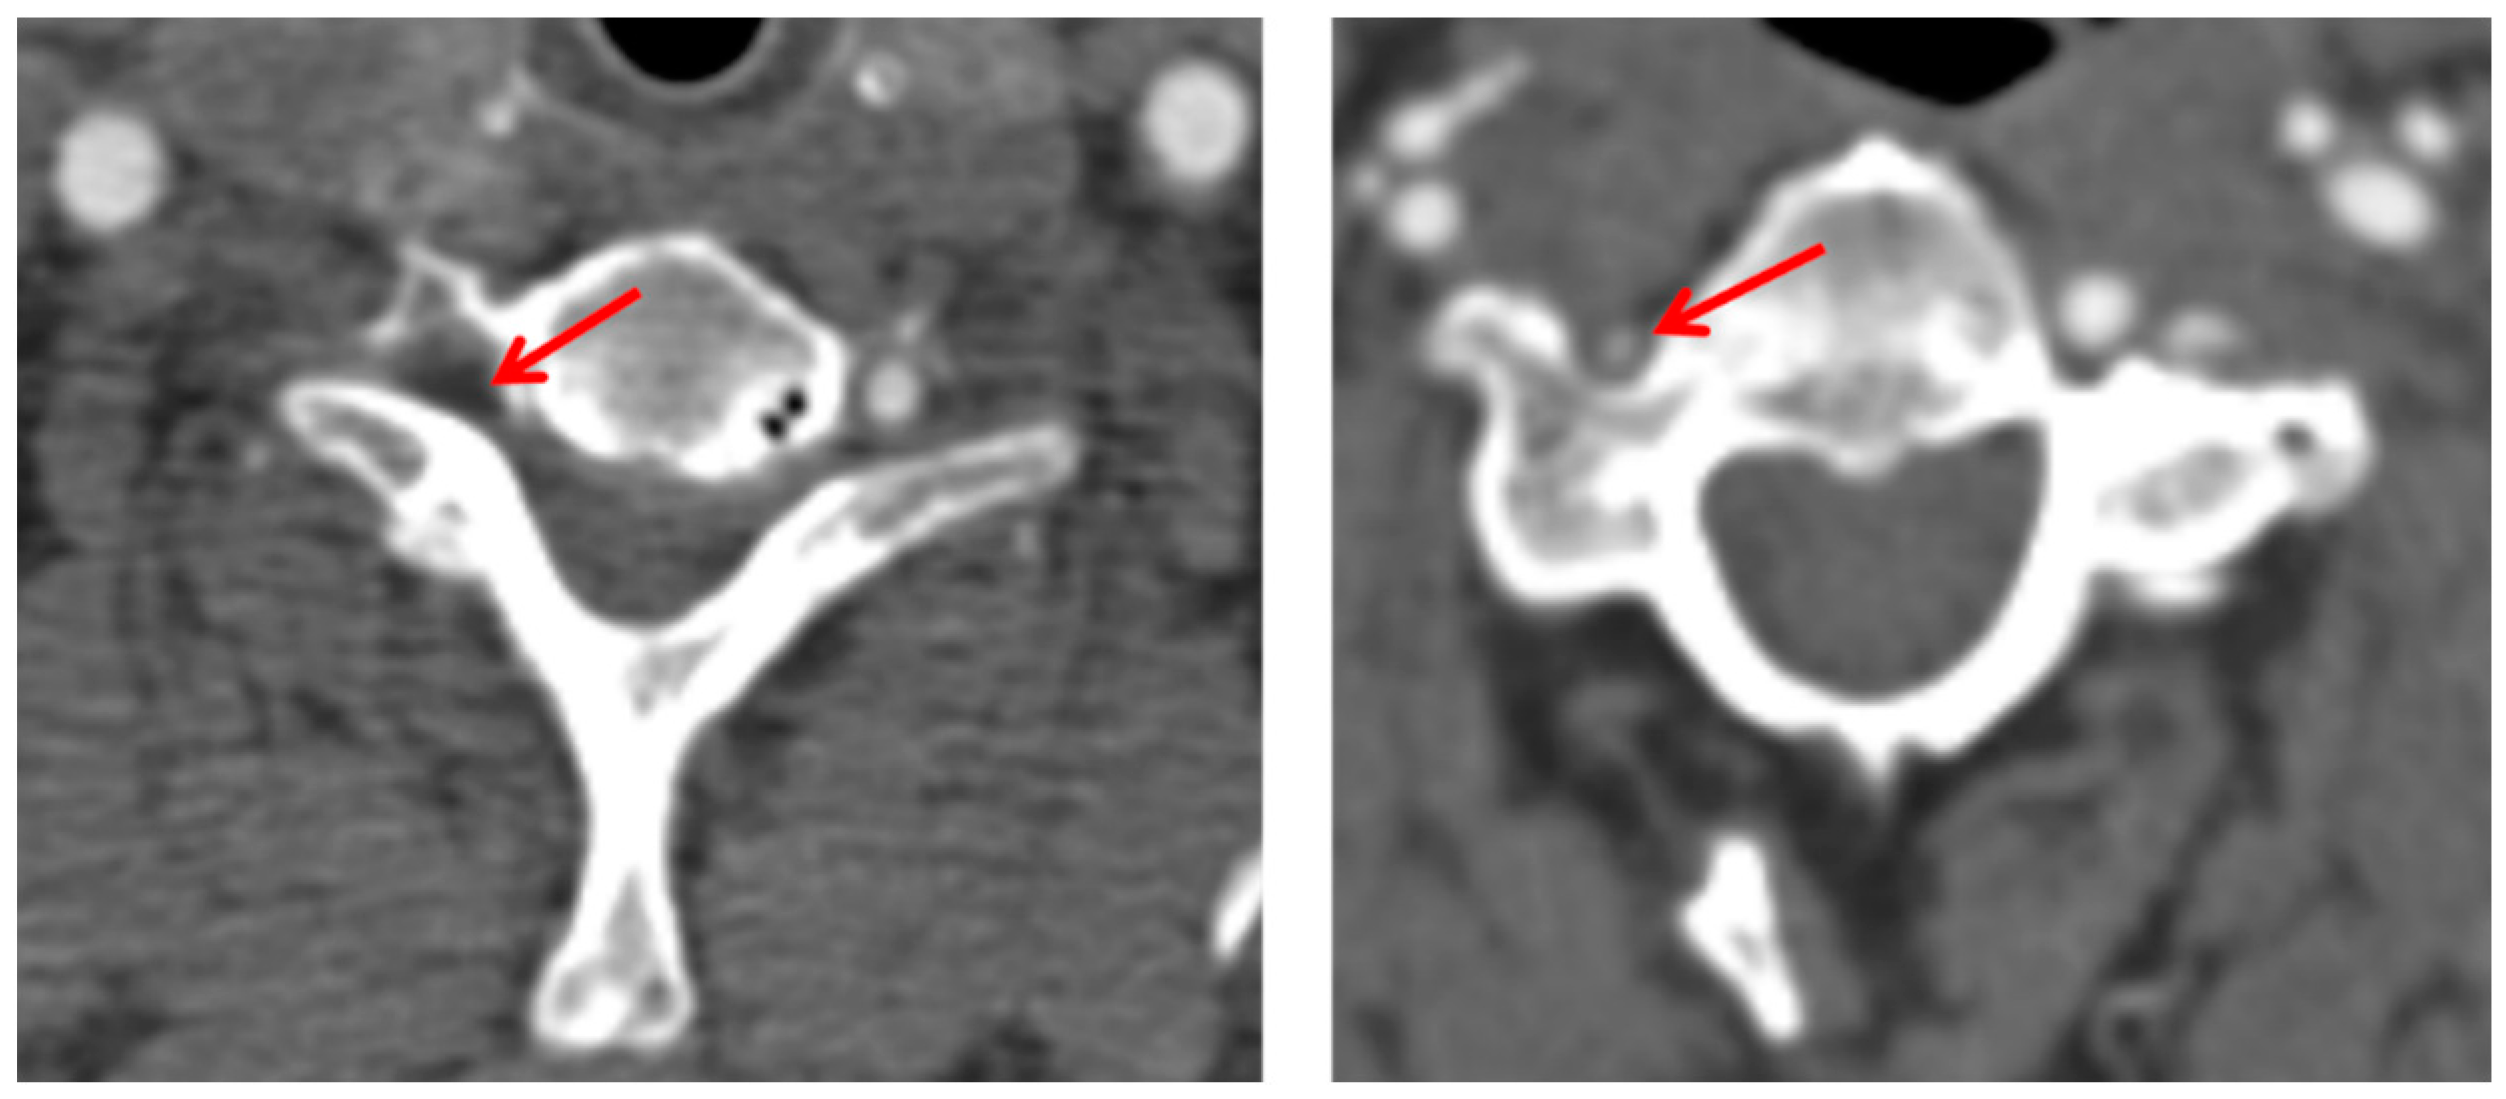

2. Case Presentation